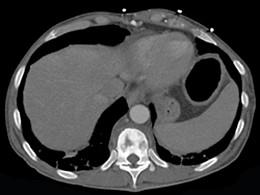

问题 男,36岁,腰背部疼痛,局部软组织肿胀,夜间加重,背部有过外伤史,有过结合图像,最可能的诊断是 ( )

选项 A、强直性脊柱炎 B、结核性骨髓炎 C、硬化型骨肉瘤 D、慢性骨髓炎 E、骨样骨瘤

答案 D